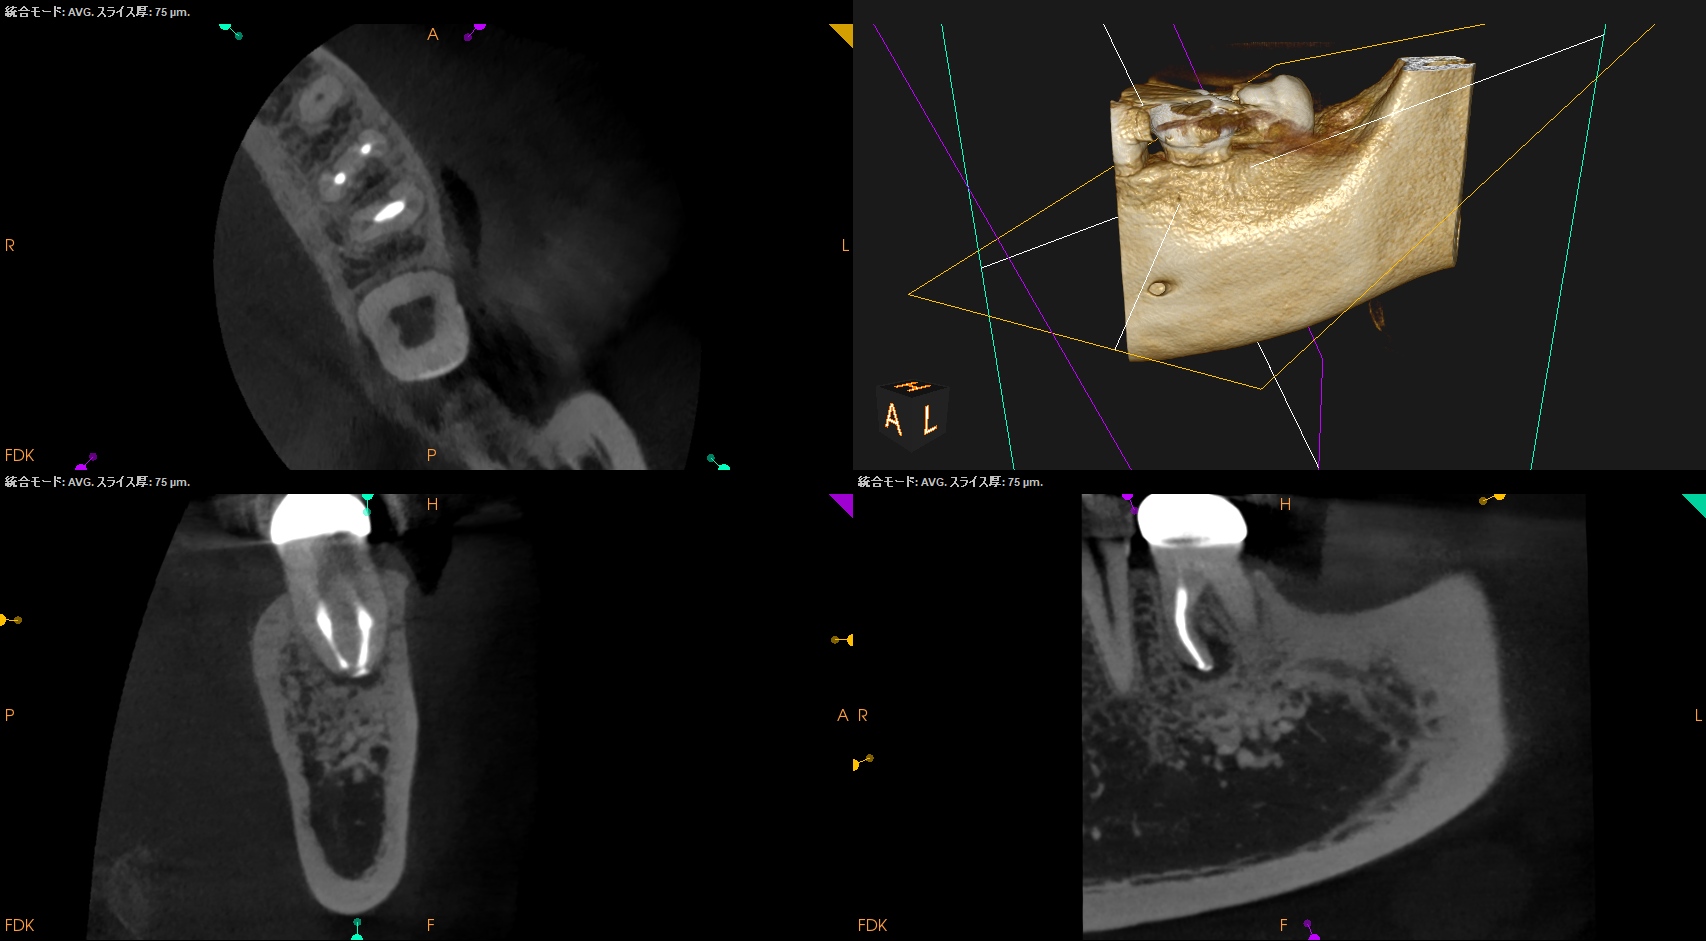

#19 M Apicoectomy(2025.1.9)

当該部位をOsteotomyした。歯槽骨は2mm削合する必要がある。

Apexを3mm削除し取り除いた。

逆根管形成はMB-MLを往復しなければならないが、

間がかなり離れているので逆根管形成には時間がかかる。

逆根管充填するが、その際はペントロンジャパンのエンドセム MTA クイックペースト Rで逆根管充填することにした。

術後にPA, CBCTを撮影した。

問題はないだろう。